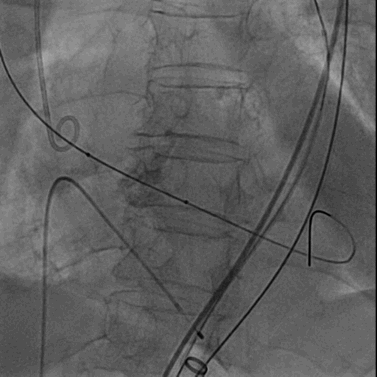

将0.014英寸导丝交换为超硬导丝后,置入22F大鞘达腹主动脉内。

经右侧股静脉沿超硬导丝置入22F大鞘达腹主动脉内